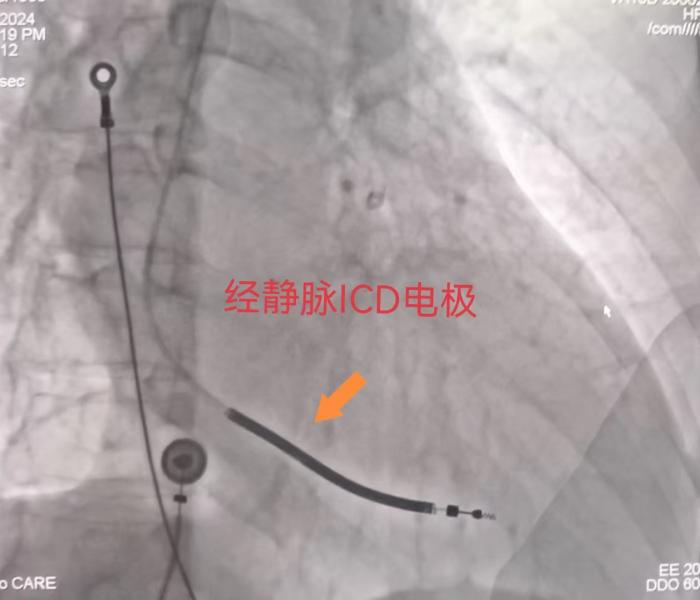

近日,湘南学院附属医院心血管内二科先后成功实施经静脉心律转复除颤器(TV-ICD)植入术和全皮下植入型心律转复除颤器(S-ICD)植入术。其中S-ICD无需经静脉路径,均埋于皮下,不影响日常活动,可避免TV-ICD所面临的导线相关并发症,也降低了系统性感染的风险,为广大病友带来福音。

因考虑蒋大娘年纪大,活动量小,同时有心脏起搏需求,适合经静脉心律转复除颤器(TV-ICD)植入术,而37岁刘先生年轻,日常活动多,无心脏起搏需求,同时合并糖尿病,为感染高危人群,适合全皮下植入型心律转复除颤器(S-ICD)植入术。周玉庆副主任医师先后为蒋大娘和刘先生顺利植入TV-ICD、S-ICD,其中S-ICD植入过程仅需半小时,术后当天患者即可下床活动。